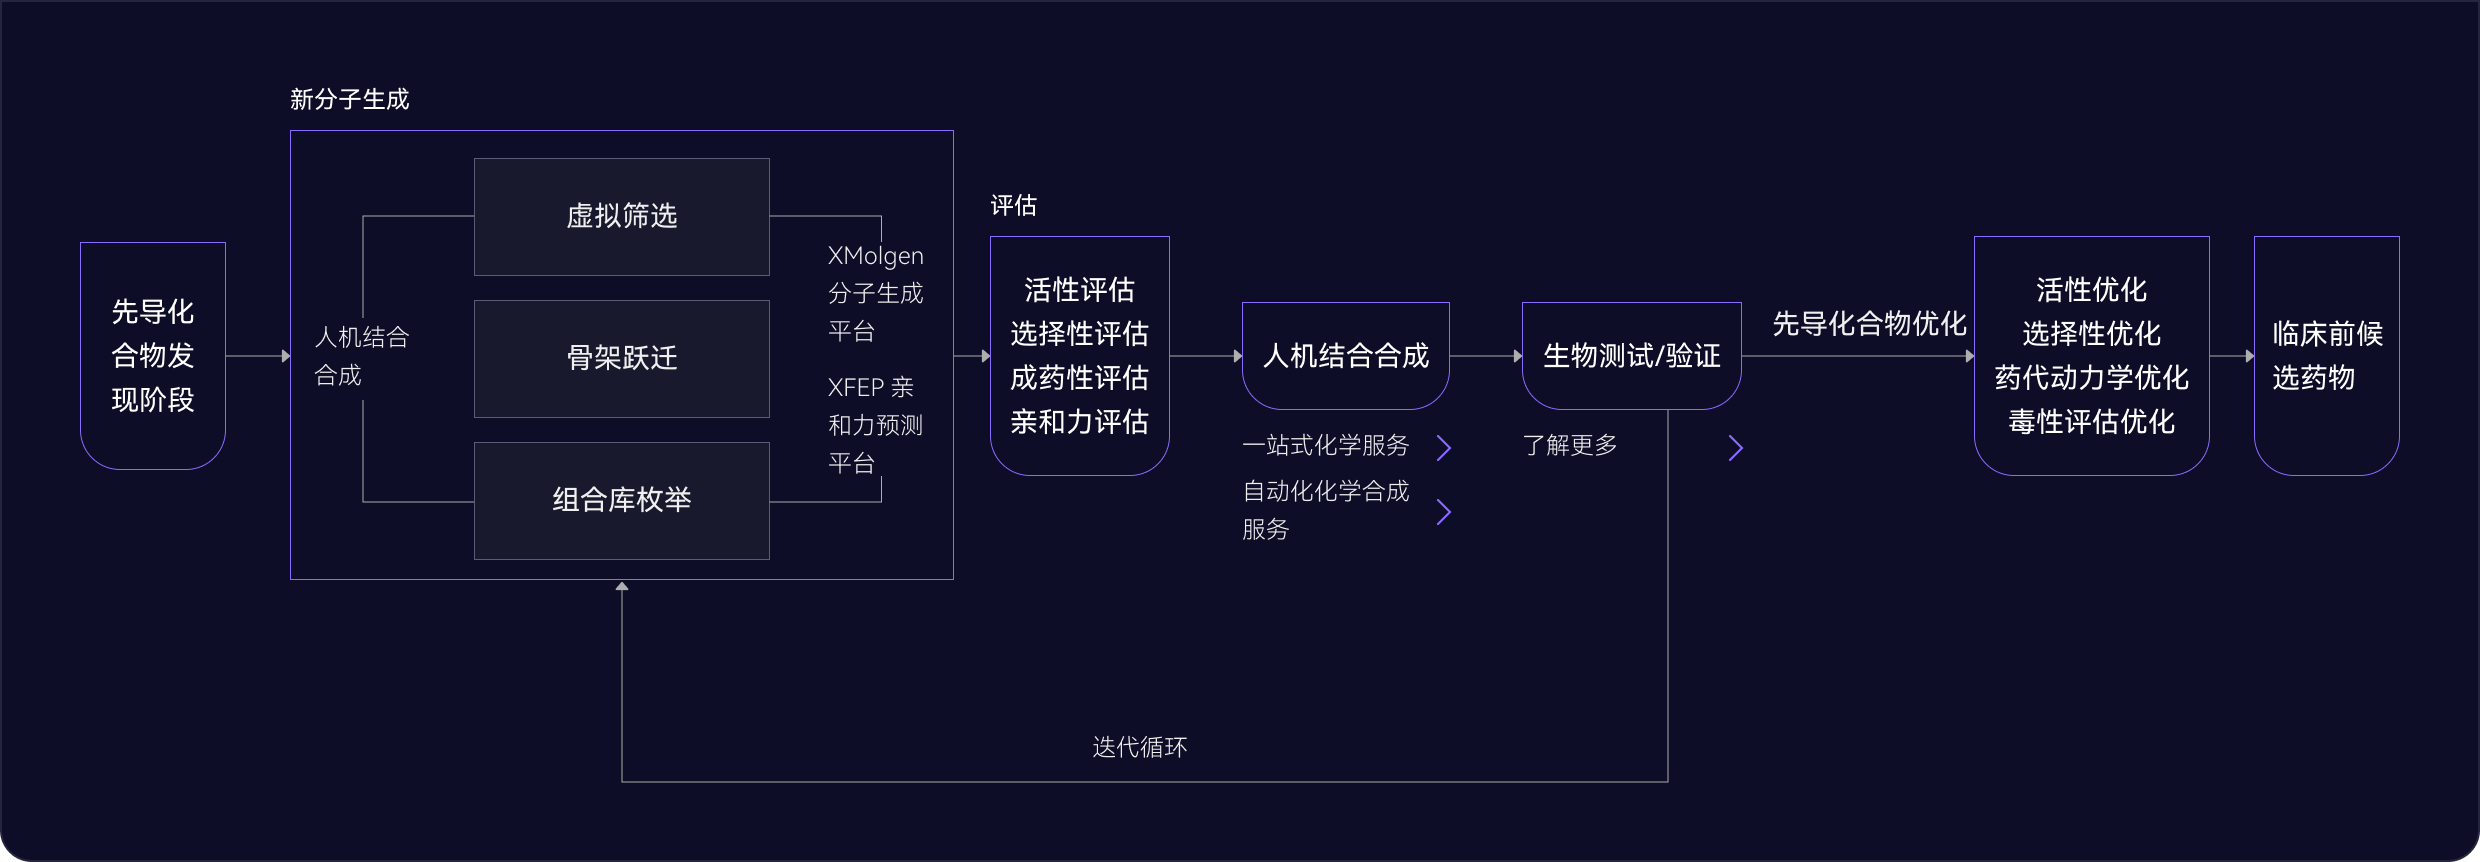

05 先導化合物階段

尋找最佳先導化合物

并優化成藥性質

先導化合物評估與優化

通過優化活性、選擇性和類藥性,將苗頭化合物轉化為先導化合物

- 利用生成式AI(XMolGen)進行分子和庫設計,增加骨架新穎性和化合物多樣性

- 通過先進的物理計算(XFEP)進行虛擬篩選,優化活性和類藥性

- 通過專有自動化平臺,實現快速且可靠的中間體和庫合成

自動化助力先導化合物優化

在進入臨床前試驗前,優化先導化合物提高療效和安全性,改善藥代動力學特性。

- 借助自動化濕實驗室化學能力,快速而穩健進行SAR分析,指導化合物設計

- 內部動物實驗室支持體內研究,包括藥代動力學/藥效學(PK/PD)、療效、安全性、劑量和代謝,推進臨床前開發

- 先進的力場技術,準確計算自由能微擾,預測結合親和力